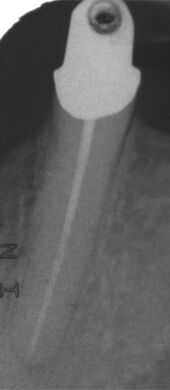

Schmerzhafter Zahn mit röntgenologisch eindeutiger Entzündung im Knochen (periapikale Aufhellung). -